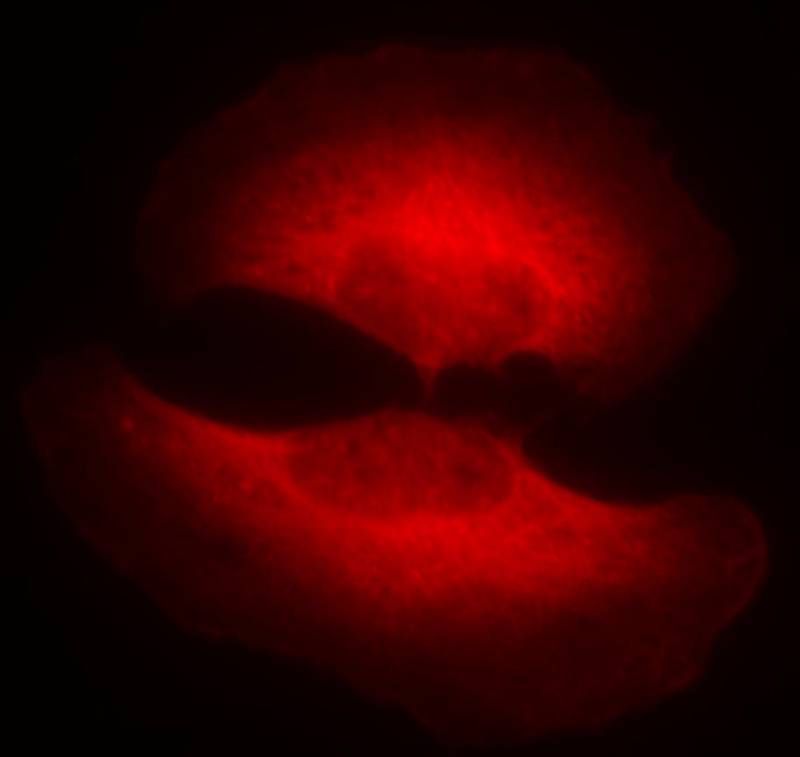

Immunofluorescence staining of methanol-fixed Hela cells showing cytoplasmic staining using GSK3β(Phospho-Ser9) Antibody #11002.

Immunofluorescence staining of methanol-fixed Hela cells showing cytoplasmic staining using GSK3β (Phospho-Ser9) Antibody #11002.